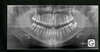

• Des anomalies prévisibles peuvent être détectées dès l'apparition de la première dent définitive (première molaire mandibulaire) voire avant. Guider les éruptions ultérieures, modeler précocement les arcades et d'autres gestes peuvent simplifier le traitement.

Une prise en charge précoce permettra de mettre en jeu toute la panoplie d'outils permettant de corriger des anomalies dentaires et osseuses et aussi réaliser une orthodontie fonctionnelle.

Il ne faut donc pas hésiter à montrer son enfant très précocement à un spécialiste en orthodontie ou orthopédie dento-maxillo-faciale. Une telle consultation doit être envisagée dès 4 ans.